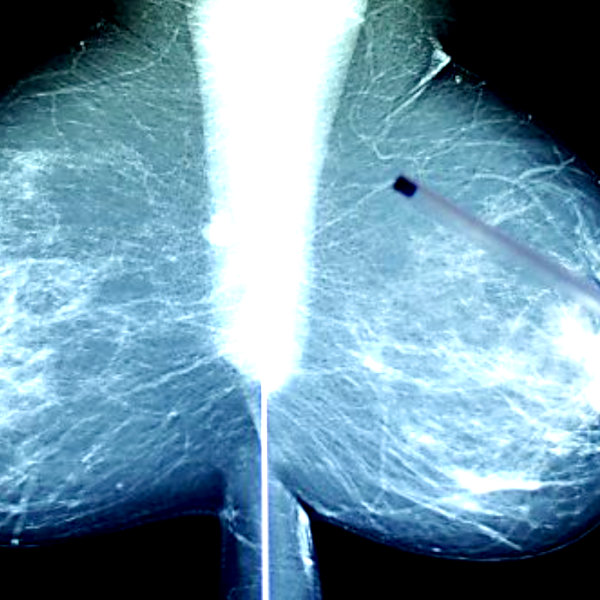

Криотерапия карциномы молочной железы

Рак молочной железы является...